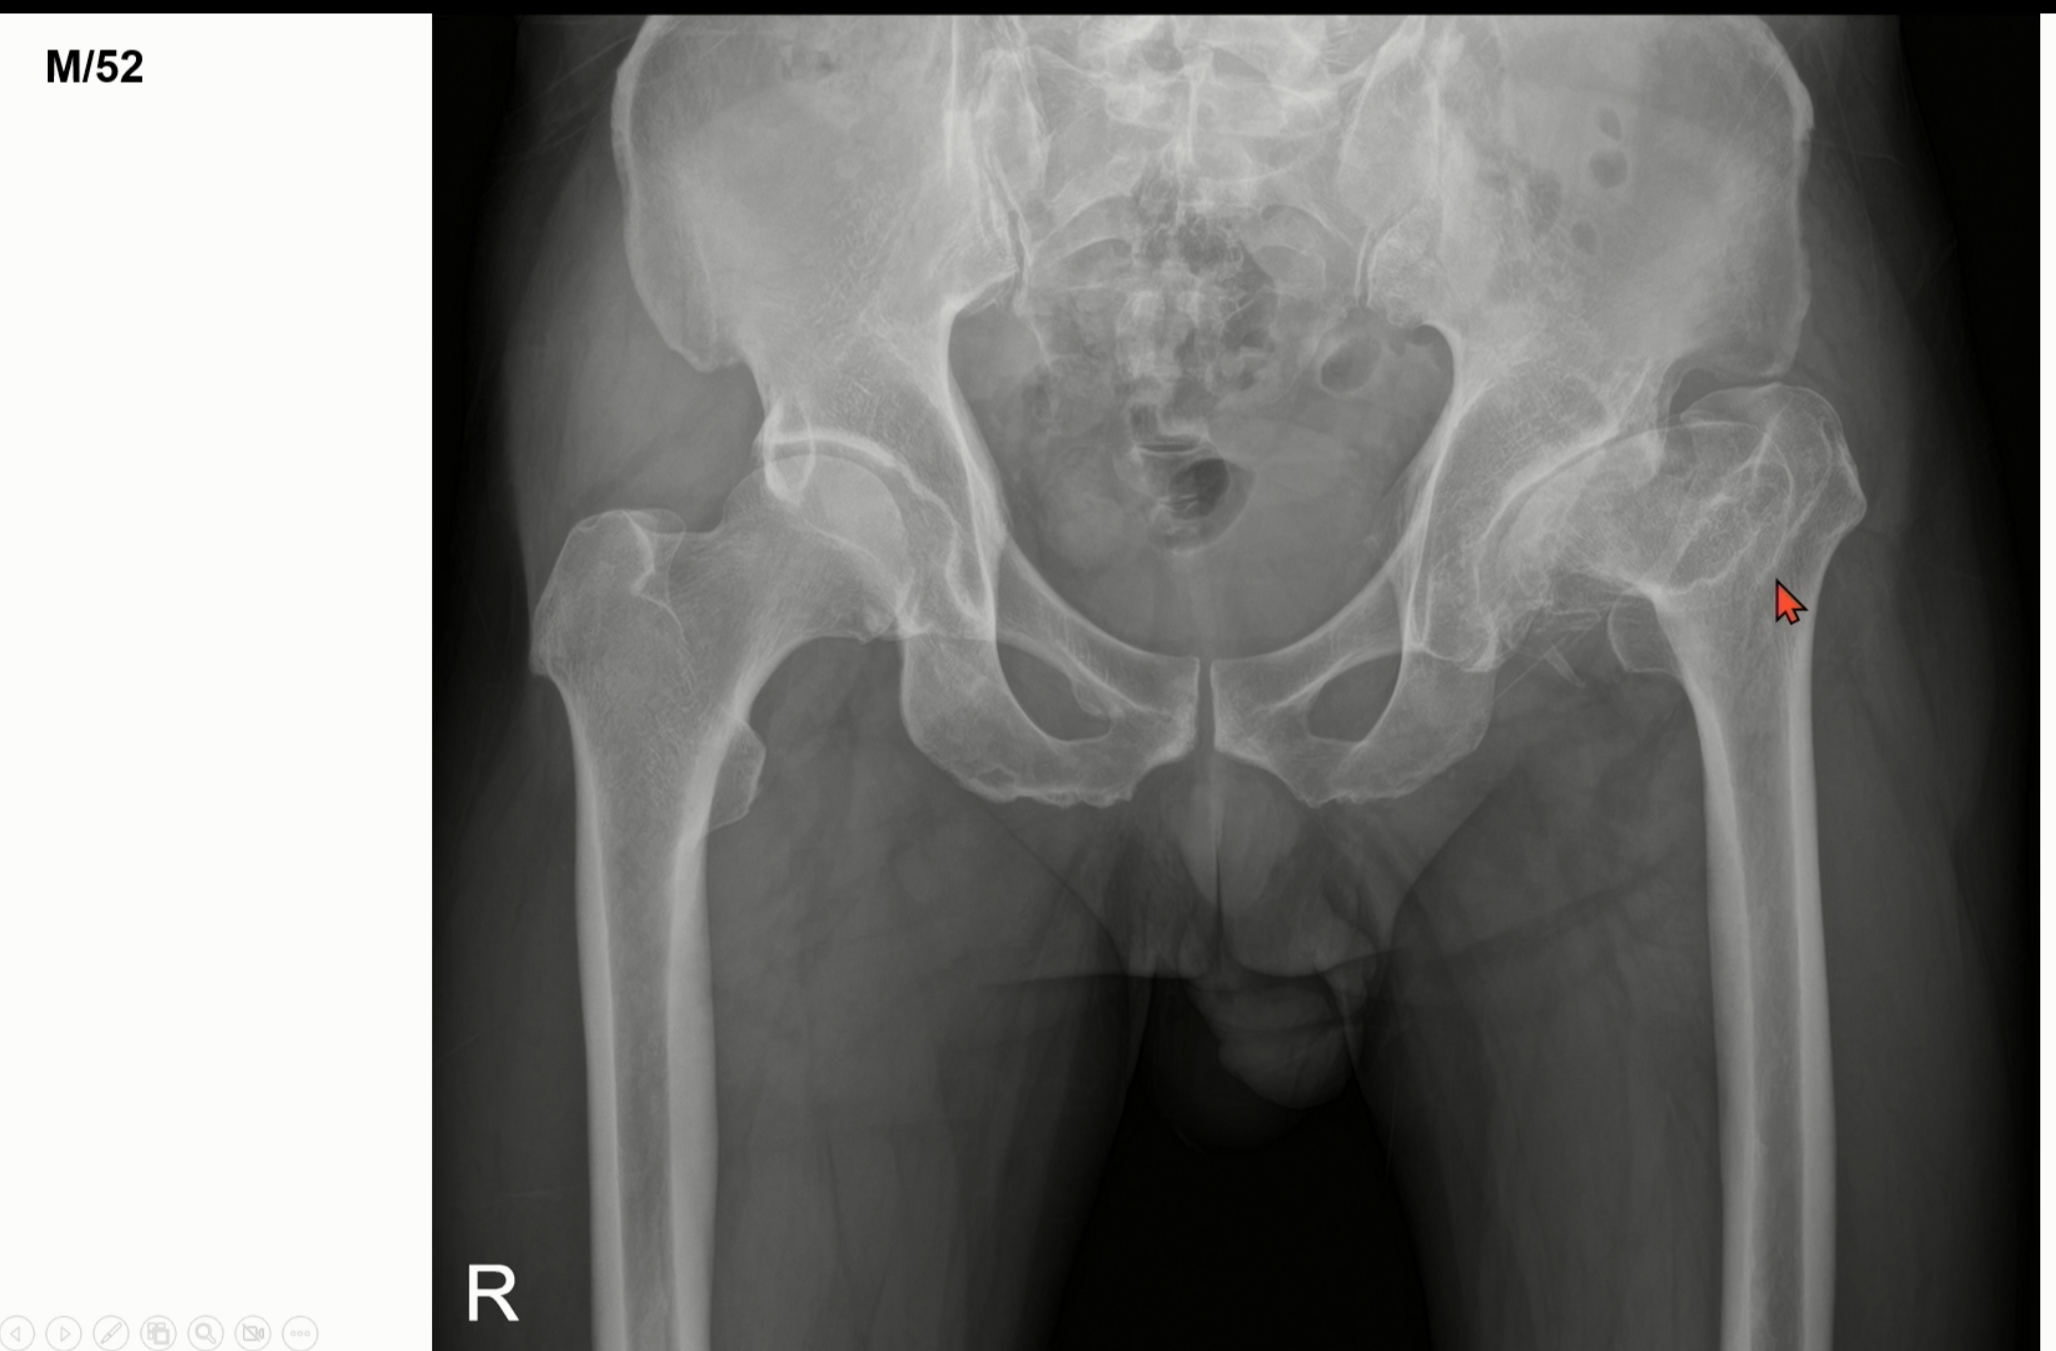

다음 사진은 위에서 보았던 사진과는 다소 다른 모습을 보입니다

이 경우에는 LCP 병의 합병증으로 골관절염이 진행된 경우입니다.

이 사진은 크게 얼핏보면, 단순 퇴행성 관절염으로 생각할 수 있습니다.

하지만, hip dysplasia로 인해서 퇴행성 관절염이 생긴 경우입니다.

이처럼 단순 노화로 인해서 퇴행성 관절염이 생긴 것이 아니라, 어떠한 원인(질병 또는 외상에 의한 합병)에 의해서 발생한 경우를 2차성 골관절염이라고 부릅니다.